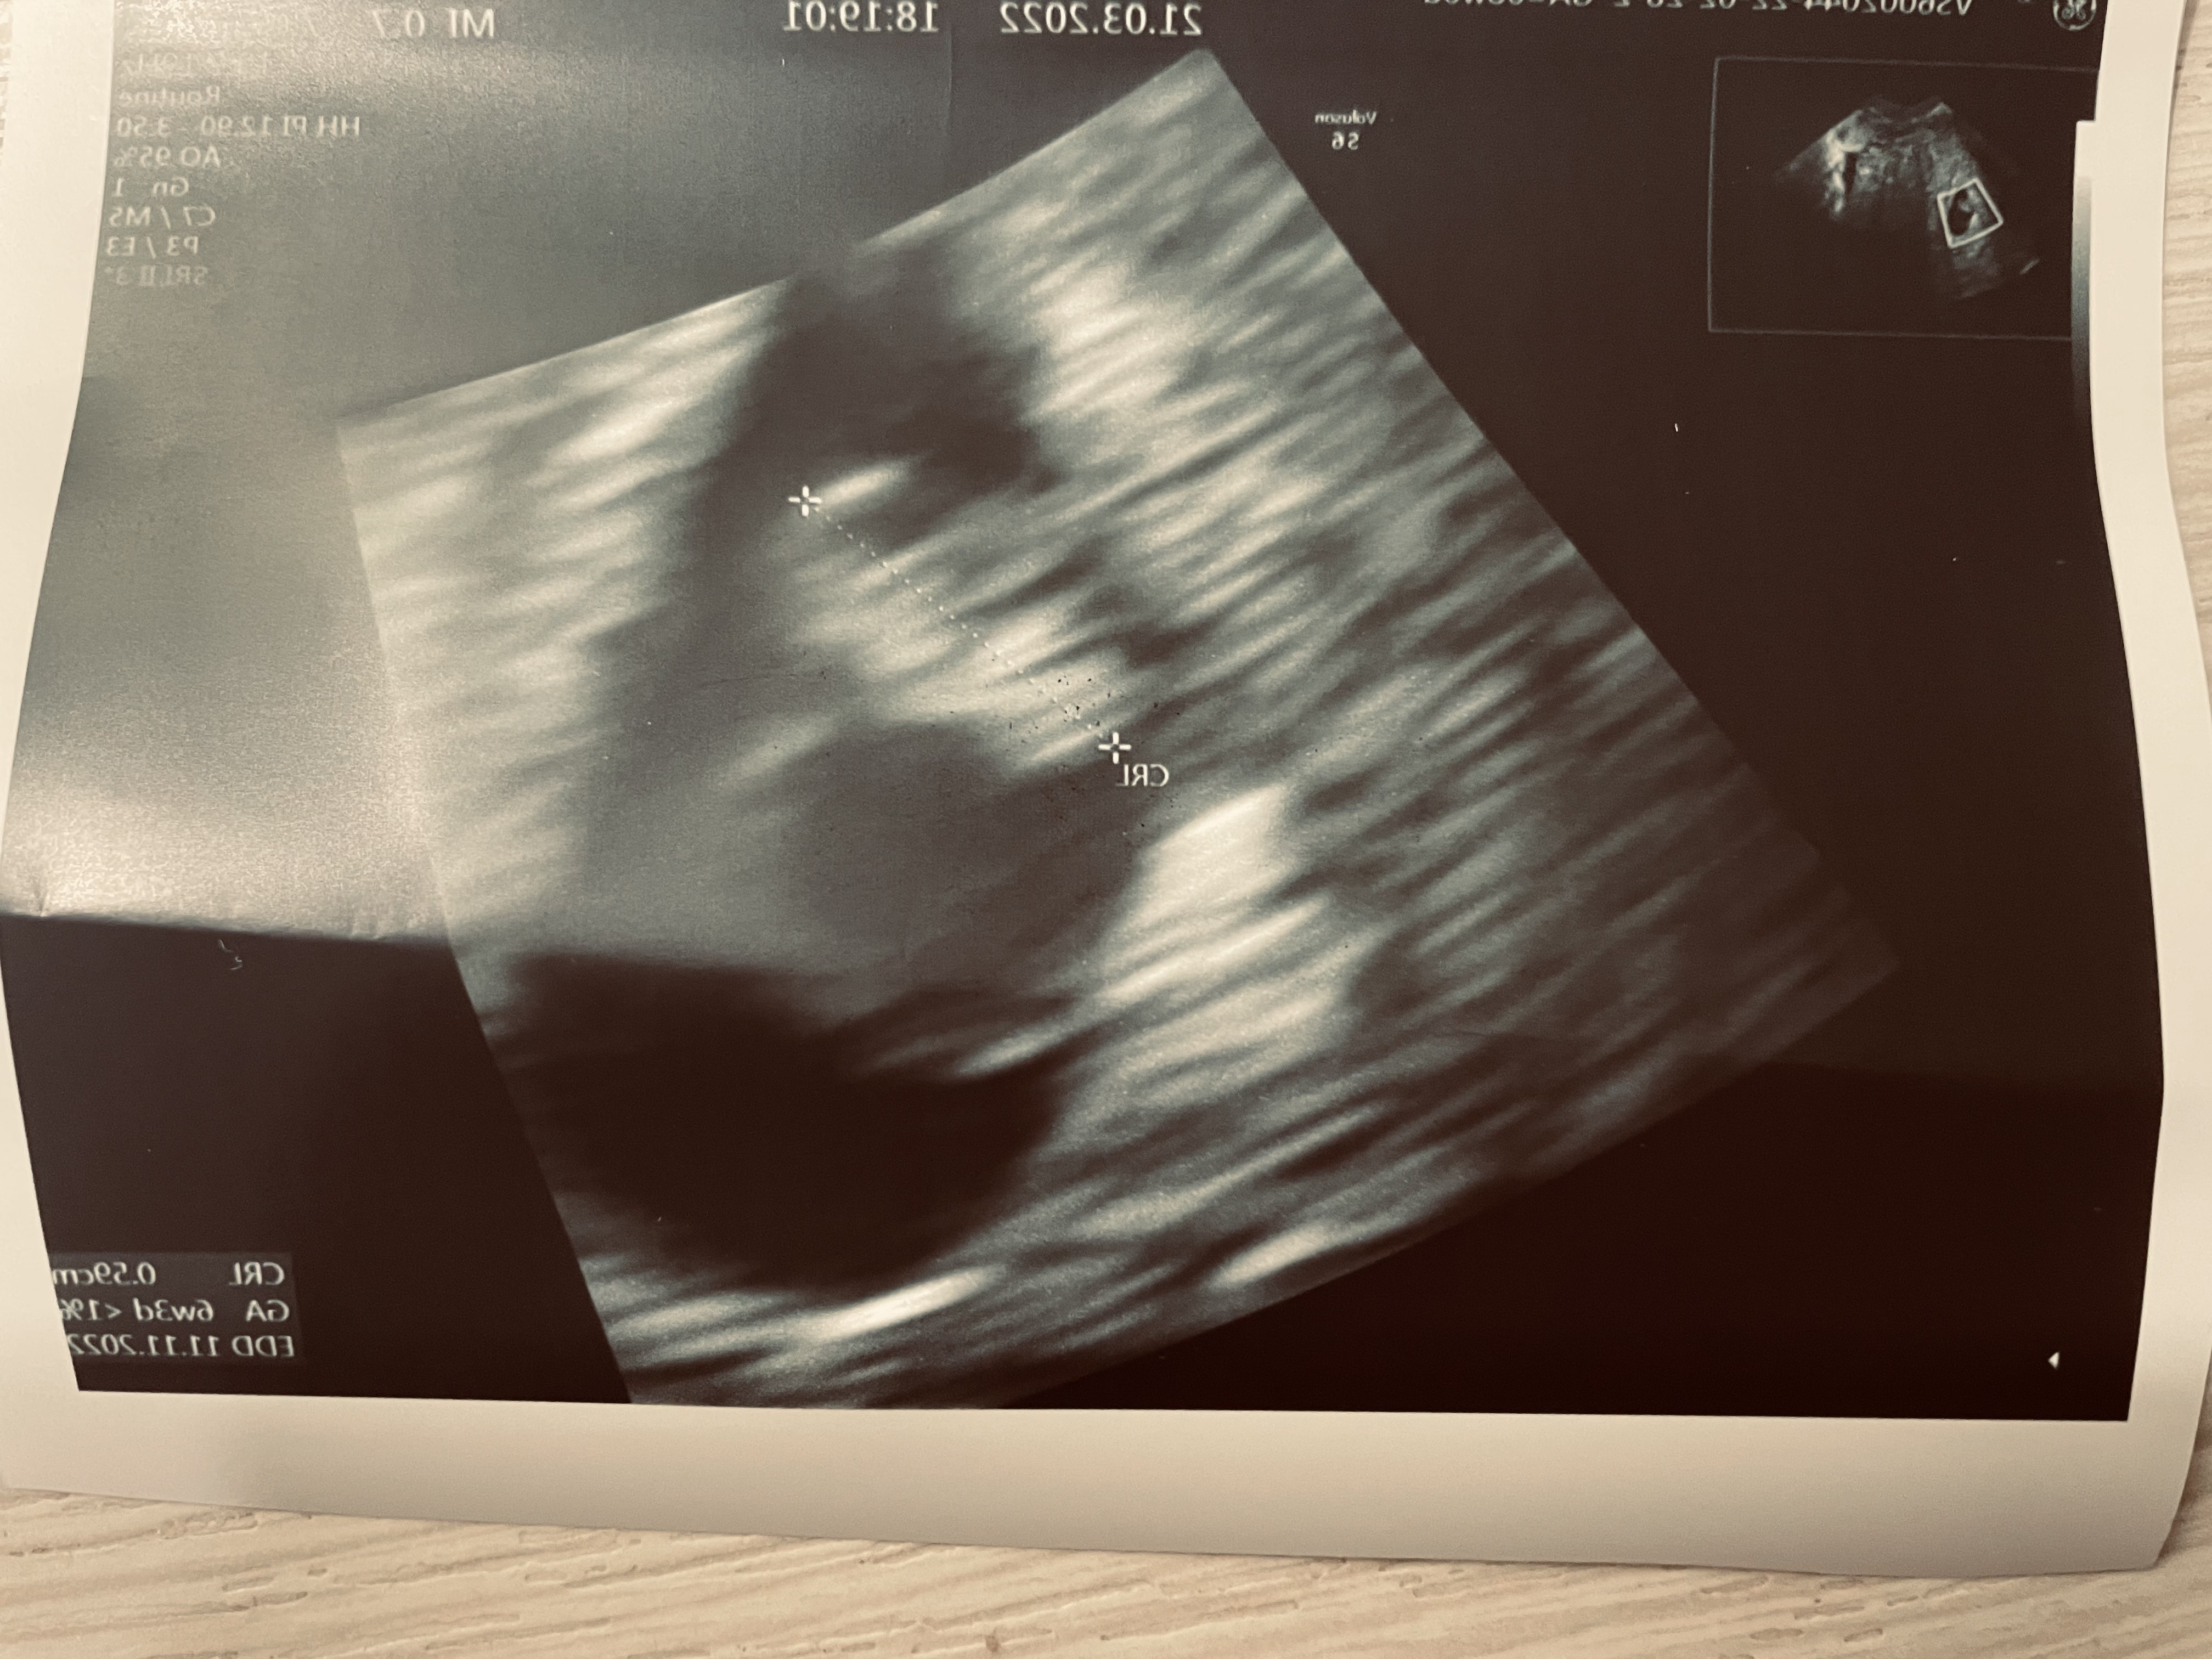

Ja już po wizycie ciąża ma 6+3 dni zarodek jest serce bije 109 uderzeń

Ale moja ostatnia miesiączka nie pokrywa się z tym co w brzuszku

Do owulacji mogło dojść później np.